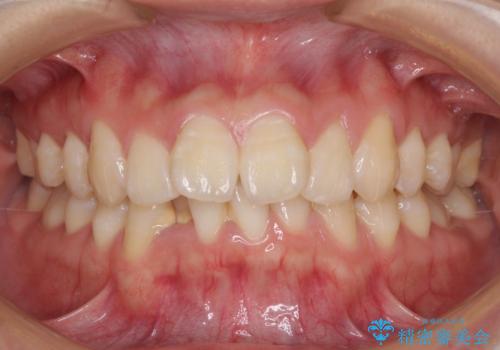

前歯のデコボコと下顎の八重歯 インビザラインによる矯正治療

担当医 藤巻太一朗